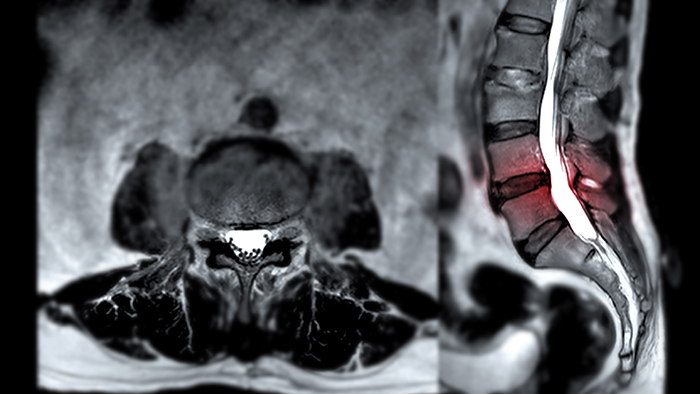

MRI คือเทคโนโลยีการถ่ายภาพทางการแพทย์ที่ใช้คลื่นแม่เหล็กไฟฟ้า (ไม่ใช่รังสี) จึงมีความปลอดภัยต่อร่างกาย และสามารถสร้างภาพโครงสร้างภายในร่างกายได้อย่างละเอียดในระดับ 3 มิติ โดยเฉพาะภาพของเนื้อเยื่ออ่อน เส้นประสาท และหมอนรองกระดูก ซึ่งเป็นจุดที่มักเกิดปัญหาในผู้ป่วยที่มีอาการปวดร้าว

- ความแม่นยำสูง: MRI มีความแม่นยำสูงกว่า 97% ในการตรวจหาความผิดปกติของระบบกระดูกและเส้นประสาท ทำให้แพทย์สามารถระบุตำแหน่งและความรุนแรงของรอยโรคได้อย่างชัดเจน

- การทำงานร่วมกับ X-ray: การวินิจฉัยที่ดีที่สุดมักต้องใช้ MRI ควบคู่กับภาพ X-ray เพื่อให้แพทย์เห็นภาพรวมของแนวกระดูก ความโค้ง และการเคลื่อนของข้อร่วมด้วย